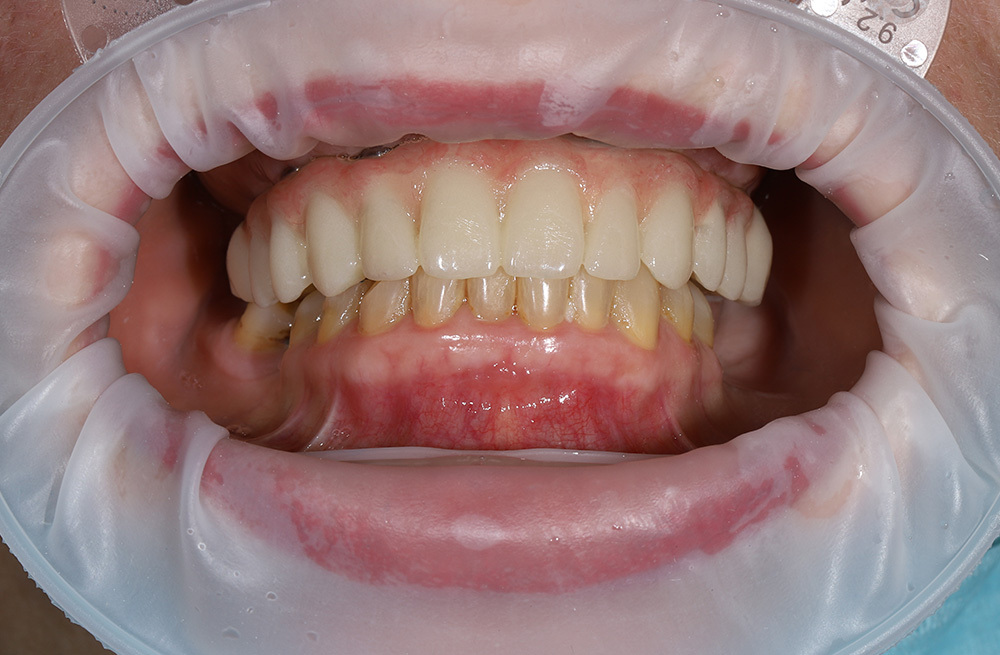

Тотальное восстановление зубов обеих челюстей